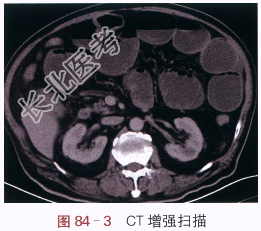

读片分析:立卧位X光平片显示多个充气扩张的小肠肠曲及液平面;CT横断面增强扫描显示小肠扩张、积液,可见气液平面,升结肠下段管壁局限性增厚伴异常强化,局部肠腔狭窄,结肠远端萎陷。